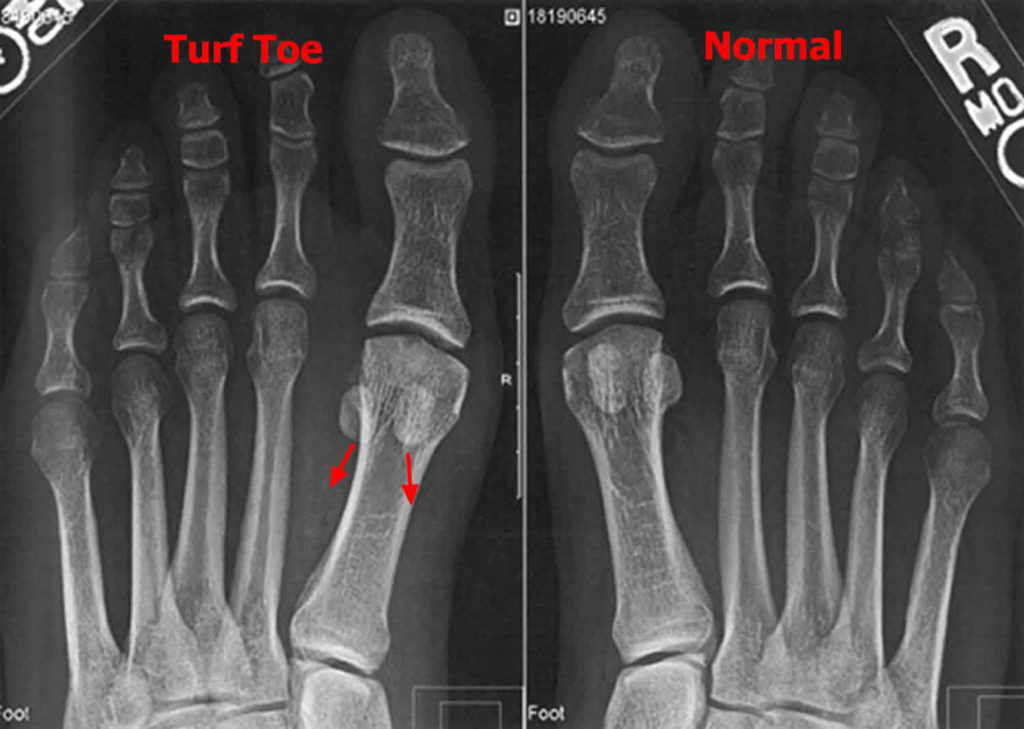

Does Turf Toe Go Away . Turf toe is a sprain of the big. Your recovery timeline and return to activity depend on the severity of your injury. The more severe the injury, the longer the recovery time will be. Grades 2 and 3 injuries take longer to heal. With severe injuries, surgery may be required. While it may sound minor, turf toe can have a significant impact on an individual’s. Sometimes complete recovery may not occur, leaving the patient with a stiff or arthritic toe. Varies depending on your pain tolerance. The recovery time for turf toe is dependent on the severity of the injury. Turf toe almost always goes away with proper treatment, such as rest and ice. Turf toe is a medical condition involving a sprain to the metatarsophalangeal (mtp) joint in your big toe. After a grade 1 turf toe injury, you can return to normal activities once your pain is under control. Turf toe happens when you bend your big toe up toward the top of your foot too far. Doctors grade turf toe injuries from 1 to 3 according to the extent of the damage to the. Treatment of turf toe will depend on how severe the injury is.

With severe injuries, surgery may be required. Your recovery timeline and return to activity depend on the severity of your injury. The recovery time for turf toe is dependent on the severity of the injury. After a grade 1 turf toe injury, you can return to normal activities once your pain is under control. Turf toe happens when you bend your big toe up toward the top of your foot too far. Sometimes complete recovery may not occur, leaving the patient with a stiff or arthritic toe. Doctors grade turf toe injuries from 1 to 3 according to the extent of the damage to the. While it may sound minor, turf toe can have a significant impact on an individual’s. Varies depending on your pain tolerance. This can cause you to sprain or injure your toe and the ligaments surrounding it.

Does Turf Toe Go Away Your recovery timeline and return to activity depend on the severity of your injury. The more severe the injury, the longer the recovery time will be. Turf toe happens when you bend your big toe up toward the top of your foot too far. Turf toe is a medical condition involving a sprain to the metatarsophalangeal (mtp) joint in your big toe. Turf toe is a sprain of the big. Varies depending on your pain tolerance. This can cause you to sprain or injure your toe and the ligaments surrounding it. While it may sound minor, turf toe can have a significant impact on an individual’s. Your recovery timeline and return to activity depend on the severity of your injury. Turf toe almost always goes away with proper treatment, such as rest and ice. With severe injuries, surgery may be required. Treatment of turf toe will depend on how severe the injury is. Sometimes complete recovery may not occur, leaving the patient with a stiff or arthritic toe. The recovery time for turf toe is dependent on the severity of the injury. Doctors grade turf toe injuries from 1 to 3 according to the extent of the damage to the. Grades 2 and 3 injuries take longer to heal.